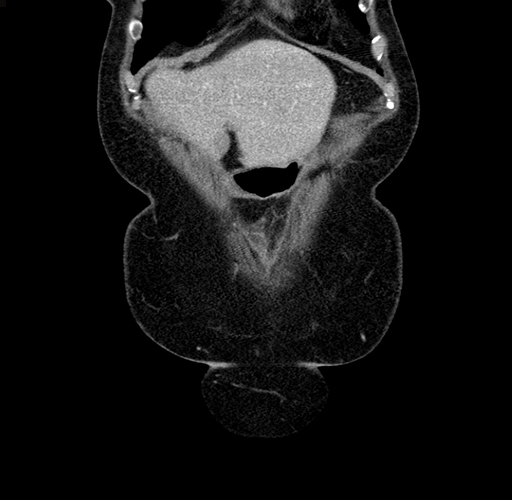

Pre-Chemo: Coronal Venous

Coronal Venous